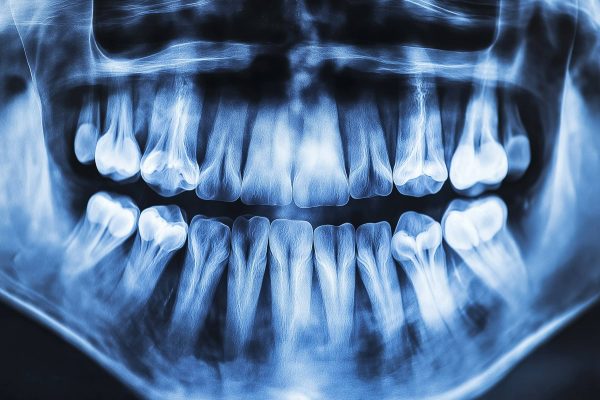

Imagerie Dentaire